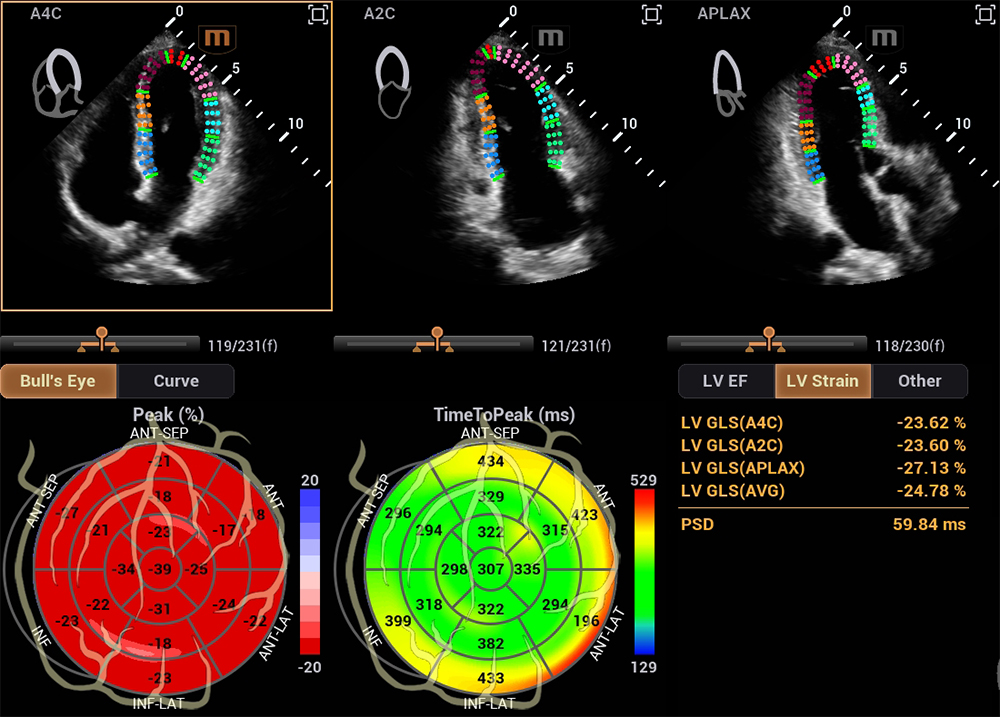

在研发中,迈瑞研发团队另辟蹊径,推出了自动左心室应变评估 Auto Strain LV 。该功能不再依赖心电信号作为“时间坐标”,而是让 AI 直接识别心脏机械运动的关键节点——当二尖瓣关闭、主动脉瓣开放,这些瓣膜运动的瞬间,就是心脏收缩与舒张的自然锚点。

自动左心室应变评估 Auto Strain LV(非心电触发)

同时,这项技术的数据直接源于机械运动的时相判定,没有电信号干扰与延迟误差,更真实地反映心脏“做了什么”。有效避免了心律失常、起搏器植入、幼儿及急诊术中等场景下,心电信号出现缺失、干扰的影响。

目前,在“非心电触发心肌应变成像多中心研究”项目中,该项技术已经获得全国 27 家医院共 2000 余例临床验证,验证了新技术的可靠性。同时,该多中心也建立首个基于中国人群的非心电触发心肌应变正常参考值,为精准诊断提供本土化“中国尺”。